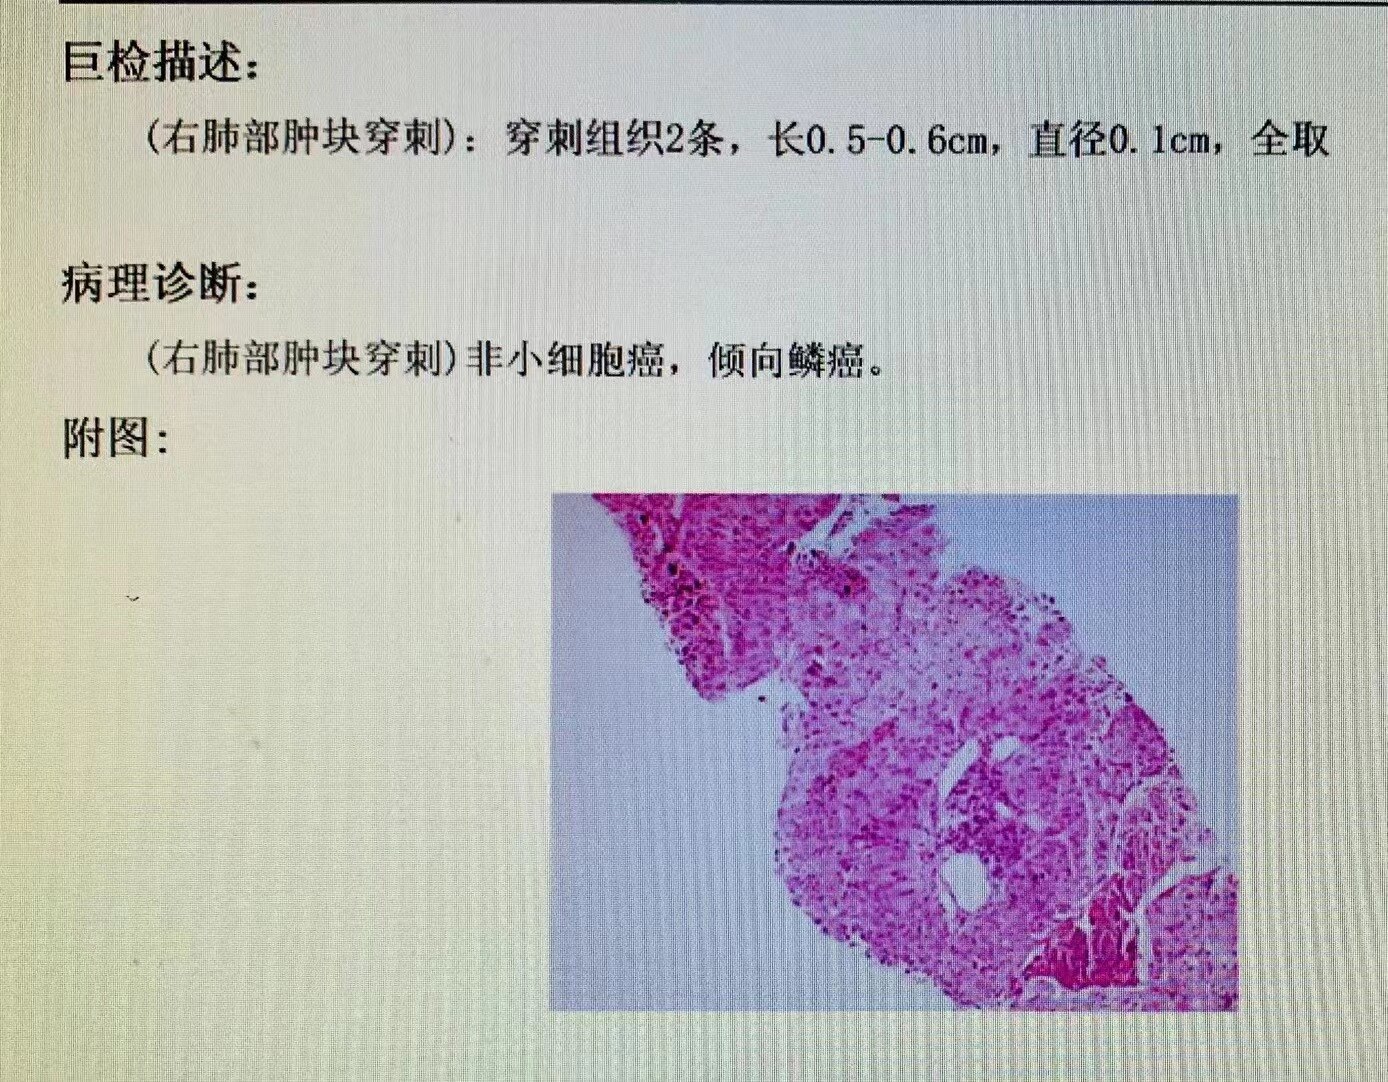

经过严密术前准备,缜密的穿刺入路选择, 最后肺穿刺✅顺利完成,肺癌确诊,完成靶向基因、免疫检测,进入治疗阶段......

肺穿刺后病理确诊肺癌